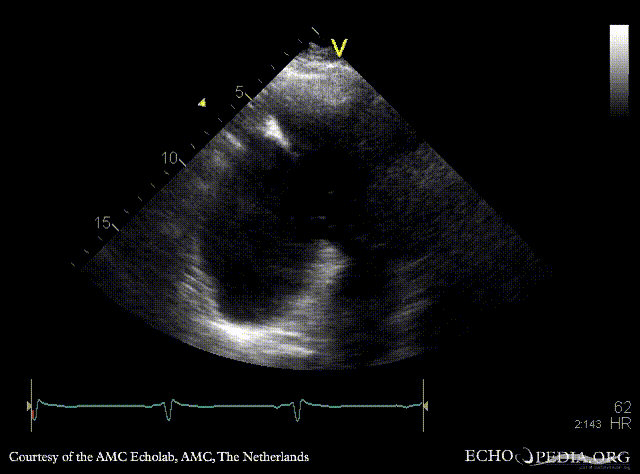

Large pseudoaneurysm of posterior wall

PLAX: large pseudoaneurysm of posterior wall PLAX: Color Doppler, severe mitral regurgitation